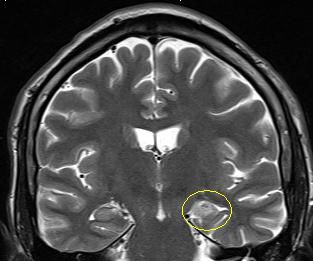

Es handelt sich um ein bildgebendes Verfahren, bei dem die Patienten in einer Röhre liegen und währenddessen mit Hilfe von wechselnden Magnetfeldern nach einem speziellen Epilepsie-Protokoll Bilder des Gehirns gemacht werden. So können Tumoren, Fehlbildungen oder andere Veränderungen des Gehirns, die Anfälle verursachen können, sichtbar gemacht werden. Durch moderne computergesteuerte Nachbearbeitungsmethoden oder Überlagerung mit anderen Bildmodalitäten können Läsionen dann noch besser dargestellt werden.

Folgende Veränderungen oder Erkrankungen des Gehirns werden häufig und mit gutem Erfolg (70-80% Anfallsfreiheit) epilepsiechirurgisch behandelt:

Tumoren

Hippocampussklerose

Fokale

cortikale Dysplasie

Umschriebene Fehlbildungen der Hirnrinde